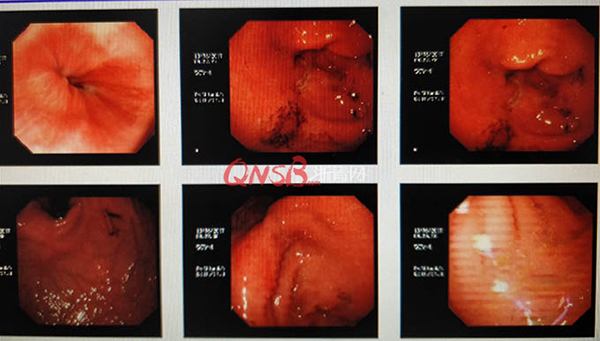

檢查結(jié)果出來(lái)后,小周大吃一驚,本以為自己的胃很健康,卻不想胃粘膜廣泛充血糜爛,長(zhǎng)了兩個(gè)巨大的潰瘍(直徑大于2厘米),還有出血和咖啡色血痂。